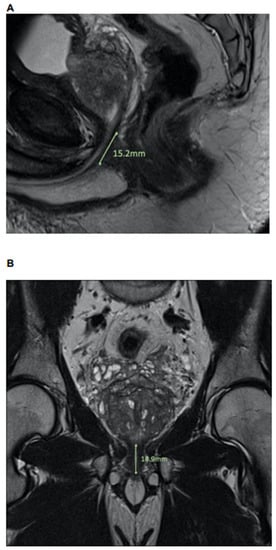

2.2. MpMRI: Lee-Type Definition and Urethral Sphincter Length

Length of urethral sphincter, coronal, in mm Median (IQR) | 14.7 (13.0, 16.7) | 15.0 (13.7, 17.1) | 14.5 (12.2, 16.2) | 0.2 |

Length of urethral sphincter, sagital, in mm Median (IQR) | 15.1 (12.8, 16.8) | 15.1 (14.1, 17.0) | 15.3 (10.8, 16.7) | 0.4 |